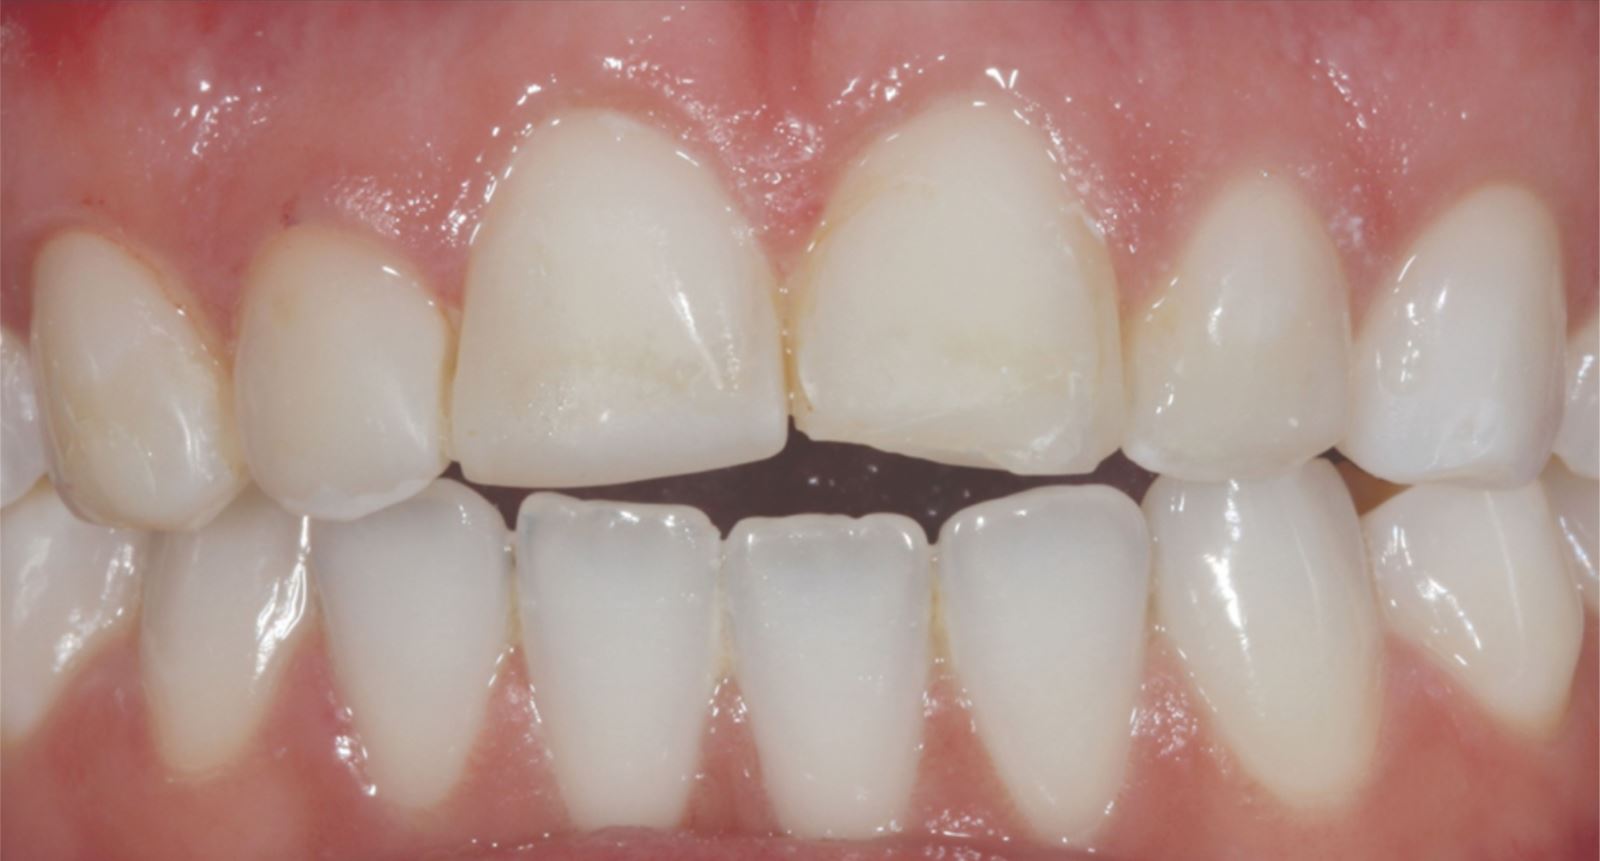

Mladá žena vo veku okolo 20 rokov, ktorú trápila diskolorácia horných frontálnych zubov po skoršej traume, vyhľadala ošetrenie u Dr. Jaleeny Fischer-Jessop, DDS, MBA. Hľadala riešenie, ktoré by obnovilo jej úsmev. Pacientka bola ošetrená konzervatívnou a cenovo dostupnou metódou: kompozitnými fazetami bez preparácie, priamym bondingom. Dr. Fischer-Jessop zvolila tento postup na prekrytie diskolorácie a zjednotenia horných zubov s dolnými frontálnymi – bez nutnosti invazívnejších výkonov, ako sú implantáty, alebo nákladných laboratórne zhotovovaných faziet. Na zosvetlenie zubov boli vybrané odtiene B1D a Enamel White (EW) a odtieň Universal Body (UB) kompozitu Transcend™ bol použitý na prirodzené splynutie okraja v cervikálnych oblastiach.

Pacientka mala výrazné estetické obavy a súčasne bola finančne limitovaná. S ohľadom na tieto okolnosti boli zvolené kompozitné fazety bez preparácie ako vhodné riešenie.

Tento postup úspešne vyriešil estetické obavy pacientky prekrytím diskolorácie horných frontálnych zubov a dosiahnutím prirodzeného, vyváženého vzhľadu vo vzťahu k dolným frontom. Použitie kompozitných faziet bez preparácie poskytlo konzervatívne, vysoko efektívne riešenie, ktoré rešpektovalo finančné možnosti pacientky a jej požiadavku na minimálne invazívny prístup.